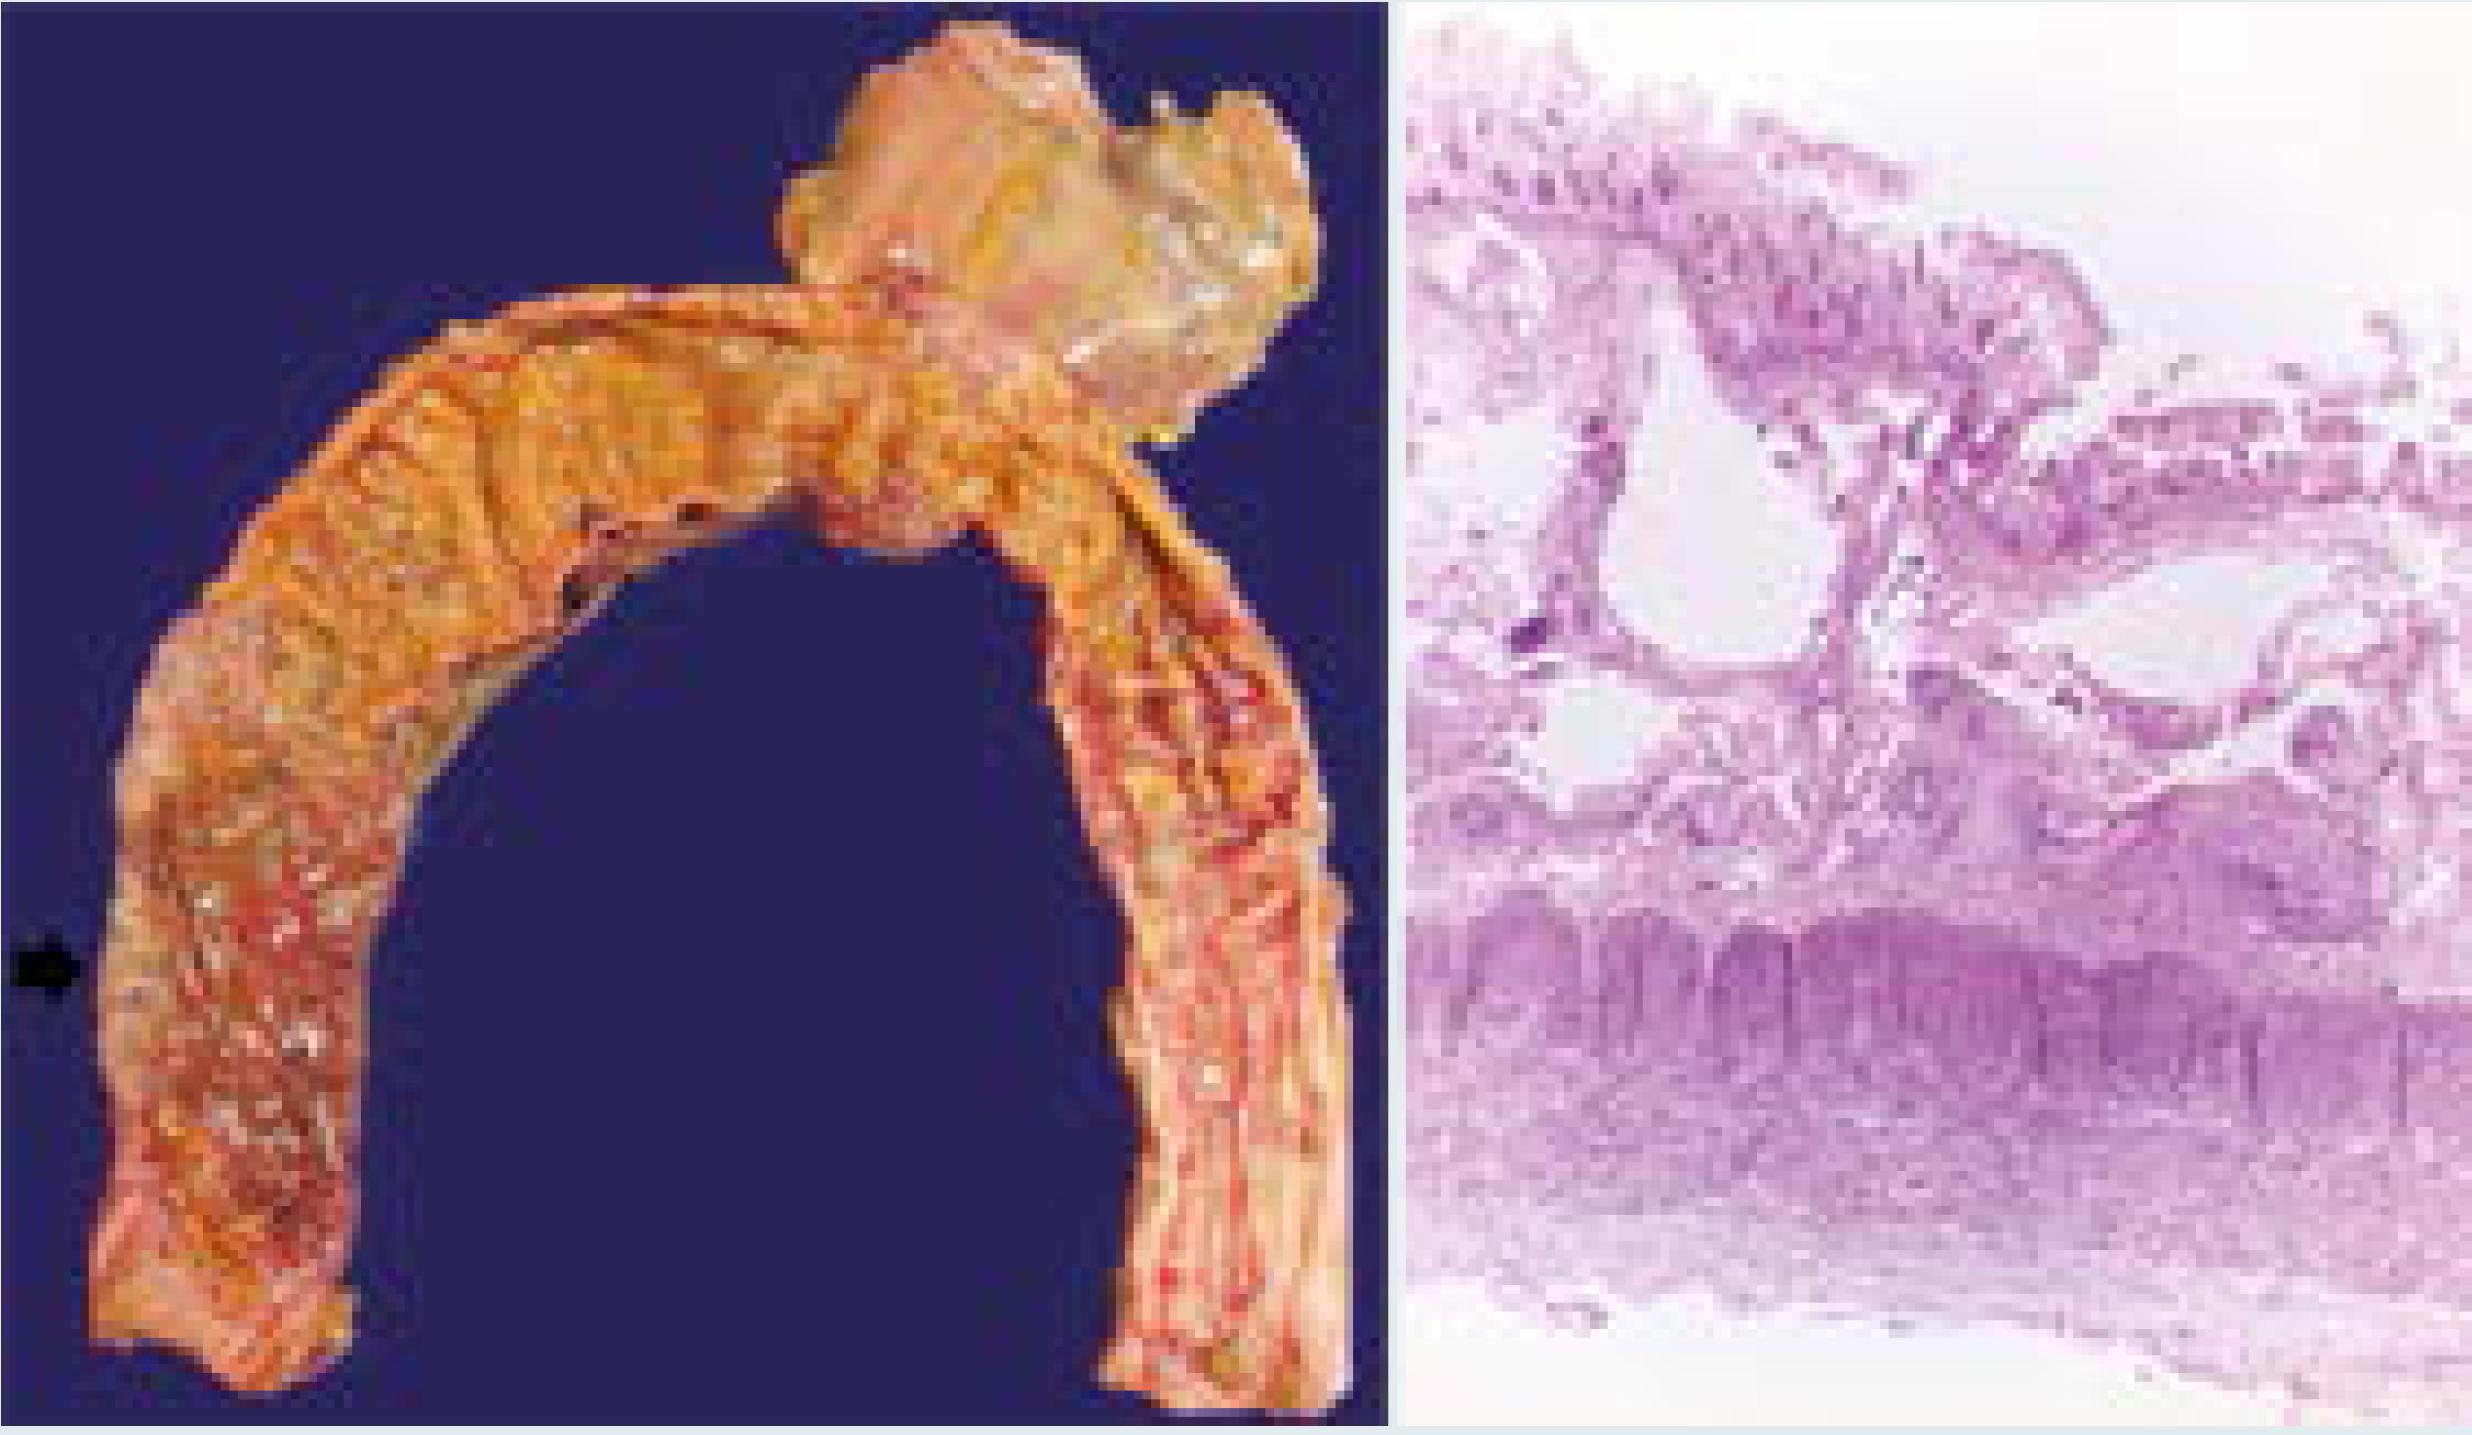

Como parte de las complicaciones el paciente tuvo enterocolitis necrosante con neumatosis intestinal, perforación intestinal, peritonitis aguda fibrinopurulenta y adherencias firmes de colon transverso con el diafragma (Figura 3).

Figura 3 Colon con mucosa de aspecto en burbujas y serosa adherida al diafragma, histológicamente la mucosa tiene necrosis y hay neumatosis intestinal.